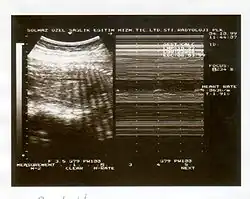

Il se réalise au cours d'une échographie, qui recherchera 5 critères (durant 30 minutes), un critère présent comptant pour 2 points (et 0 s'il est absent) :

- réactivité du rythme cardiaque fœtal,